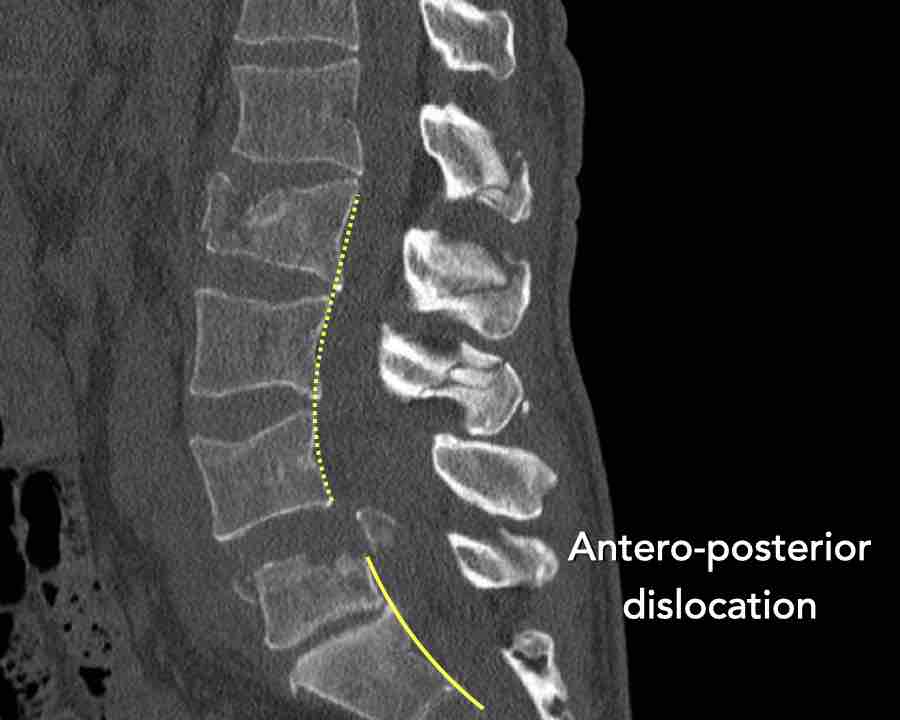

Type C Translational injuries

We start with the most severe injury and work from there.

Translational injuries are dislocation or displacement of a vertebral level from the level below or above.

There are no subtypes because various configurations are possible.

There is a high degree of instability and therefore an indication for surgery.

Images

This is a clear example of translation in the anterior direction.

Conclusion

Type C injury.